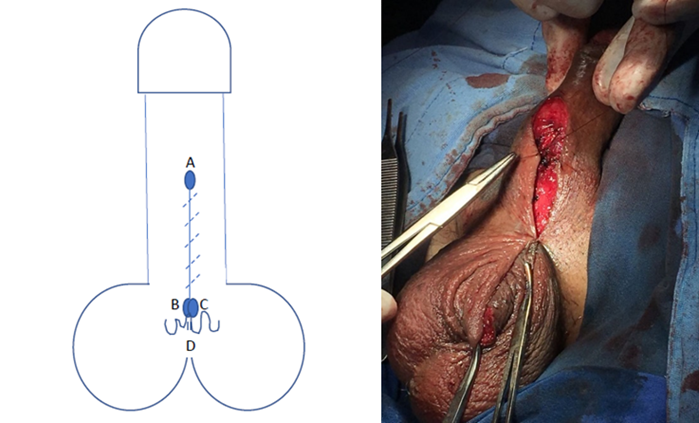

Se realiza protocolo prequirúrgico con documentación completa en el expediente clínico, ingreso del paciente para cirugía ambulatoria, con valoración anestésica, ayuno de 8 horas, baño previo al procedimiento, no se administró antibiótico profiláctico por no estar justificado, se realiza tricotomía según se necesite, se aplica asepsia antisepsia con iodopovidona. Se coloca lidocaína al 2% como anestésico local en el área quirúrgica en planos superficiales y profundos. La técnica quirúrgica aplicada en ambos casos se trata de una Plastia V-T, la cual consiste en realizar una incisión sobre la cuerda en forma de v invertida para despegar las capas de la piel de su adherencia aberrante en la cara ventral del pene (Figura 1 y 2), se afronta la nueva base del pene con sutura absorbible (Figura 3 y 4) , posteriormente se realiza incisiones laterales a la base del pene y coincidiendo a la raíz de la piel del escroto para distribuir toda la piel escrotal sobrante de manera uniforme, esto confiere la forma final de una T invertida (Figura 5 y 6).

Figura 2 Se traza una V invertida con el vértice A en la punta de la cuerda, y B y C a los lados hacia la base del pene cara ventral.

Figura 3 Se realiza la incisión desde A a B y A a C, disecando las adherencias de la cuerda hasta la base del pene, quedando la piel del escroto redundante D.

Figura 4 Se sutura B con C para formar la nueva base del pene en su cara ventral y afrontando el resto de la piel del trayecto A con B-C, quedando la piel redundante, D, debajo.

Podemos observar que posterior a la realización de la circuncisión, se realizó paso a paso la técnica propuesta como podemos observar en las Figuras 1-6 que corresponden al caso 1 que fue el más representativo de la técnica.

En la técnica propuesta se logra respetar el sentido del rafe peneoescrotal, y el la incisión horizontal permite distribuir la ganancia de la piel escrotal de una manera uniforme para que cuando el pene este en erección, la dinámica de tensión en la piel tenga piel redundante en la base y evite la formación de pliegues a la tracción, además, en las imágenes se aprecia como se logra la separación total del pene del escroto, lo cual es uno de los principios básicos de la técnica quirúrgica (Figura 2), lo cual se logra como en ninguna otra descrita.